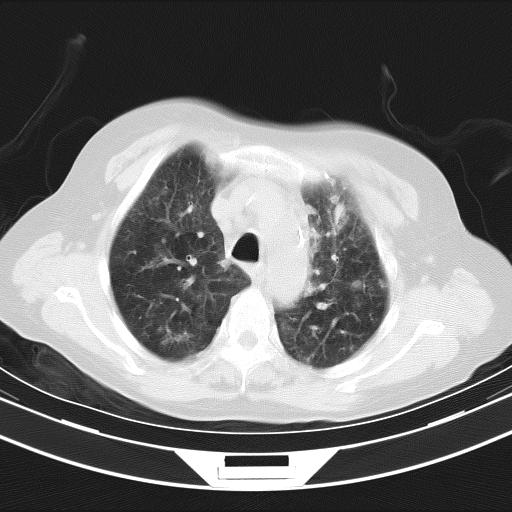

老年女性,嗜睡3天,意识模糊。轻咳,无发热。

两肺慢支炎伴感染,左侧胸腔积液。纵膈及双侧肺门淋巴结肿大建议复查。

双肺多发淡片影,毛玻璃影,,支持支气管肺炎,,建议血气找原因,,嗜睡是否肺性脑病?有没有慢支病史?

双肺炎症,建议抗炎治疗后复查,见过几个老年肺炎病例,没有发烧、咳嗽症状,直接以昏迷就诊。

1)两肺感染性病变;建议抗炎治疗后复查。2)纵隔淋巴结肿大。3)左侧胸腔积液。